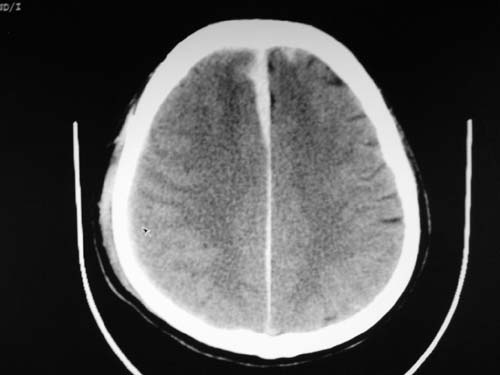

标题: CT17020:是硬膜下的吗?

脑中线内血肿,是硬膜下的吗?

硬膜下血肿,有颅骨骨折

支持镰旁硬膜下血肿,颅骨骨折,头皮损伤.

这个病人年龄不小吧,右侧脑沟不清,中线结构稍有左移,右侧额颞顶及右镰旁硬膜下血肿,另有蛛血,骨折。

外伤后引起的颅骨骨折、硬膜下血肿、皮下血肿,颅骨骨折引起的矢状窦破裂,形成大脑纵裂内血肿。